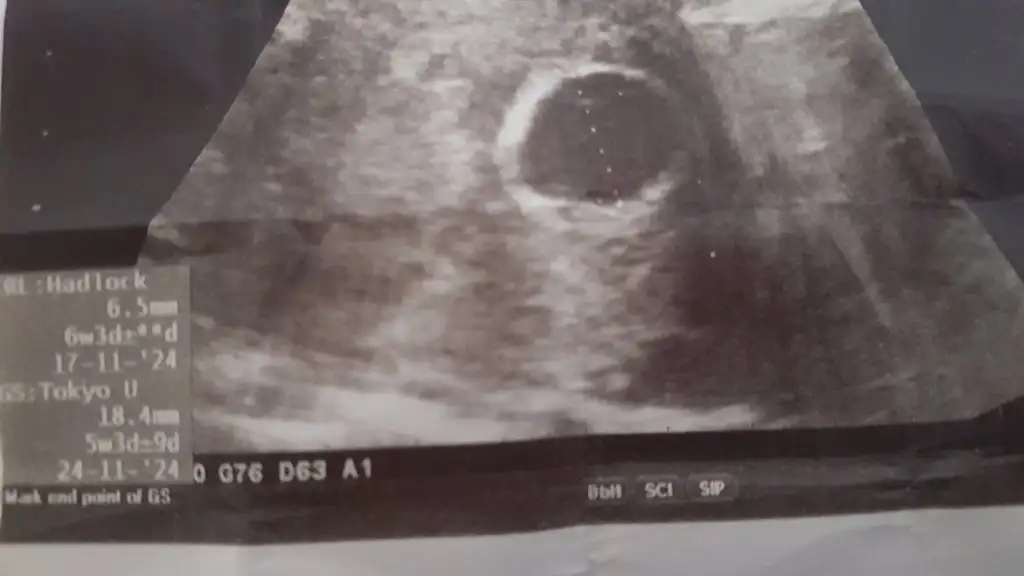

İnşallah çok teşekkür ederimYolk sac var sanki bubihtimali düşürür ama her şey olabilir tabi. Inşallah sağlıklıdır.

İnşallah dediğiniz gibidir. Çok teşekkür ederim. Umarım siz de iyisinizdirBu kese boş değil2kez boş gebelik yaşadım kesenin içi simsiyah ve boştu . Güzel haberler alın inşallah

Ben daha önce boş gebelik yaşadım ama hamilelik belirtim sıfırdı bunda mide bulantısı yaşıyorum yani göğüslerde hassasiyet var bide adet günümde kanama oldu yerleşme kanaması benim bildiğim şuan 7 hafta 6 günlük olması gereken ultrisan 5 hafta 3 günlük görünüyor diyorumki Allahtan ümit kesilmez ama daha önce yaşadığım için biliyorumSizin ultrason goruntunuz 5.haftaya mı ait? Sizinkinin de içi tam boş gorunmuyor hafif bir şey var